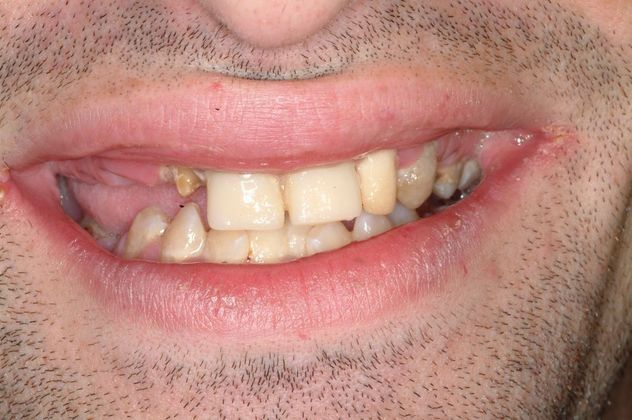

This young insurance professional had soft teeth since childhood, suffered dental neglect and was dissatisfied with his smile and wanted the best possible result. His teeth were failing but fortunately his bone was good. After extractions of all teeth and cleaning up disease, full mouth dental implants were placed and his smile and function were restored once again

Procedures : extractions, full mouth implants and full mouth reconstruction with metal-ceramic bridges.